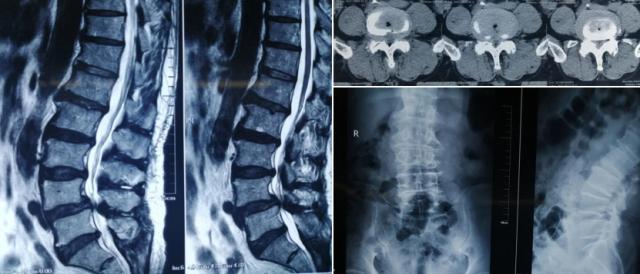

患者男性,64岁,腰痛伴双下肢麻木疼痛2年加重2月入院。被诊断为腰椎退变性滑脱,脊柱外科刘军主任带领团队结合患者病情、影像学资料并同患者及家属沟通后,采用机器人辅助下ULIF-ULBD技术为患者进行手术治疗。手术微创、精准,患者术后第一天即下地活动,效果良好。

术前影像